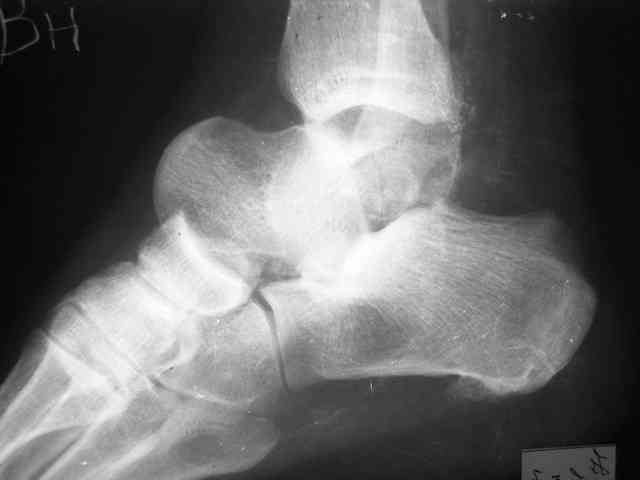

Уважаемый Александр! Как обещал представляю Р-граммы и операционные фото.

Опять надоедаю с вопросами:

Ваши (лично ваши) рекомендации - астрагалэктомия-аппаратный пяточно-большеберцовый артродез с одновременным удлинением голени - правильно?

Можно убрать таранную кость, и поместить в образовавшуюся полость либо бусы из цемента с антибиотиками, либо вылепленный прямо по форме тарана спейсер. Целесообразность этого будет определяться распространенностью гнойного процесса. Может быть, будет достаточно только удаления тарана.

Вместе с аваскулярным куском кости устранится субстрат. Надо опасаться не мягких тканей, а плохо кровоснабжаемых. Если после удаления тарана добиться контакта хорошо васкуляризованных пятки и больщшеберцовой, мягкие ткани не давить, чтобы некроза раны не было, то все должно зажить.